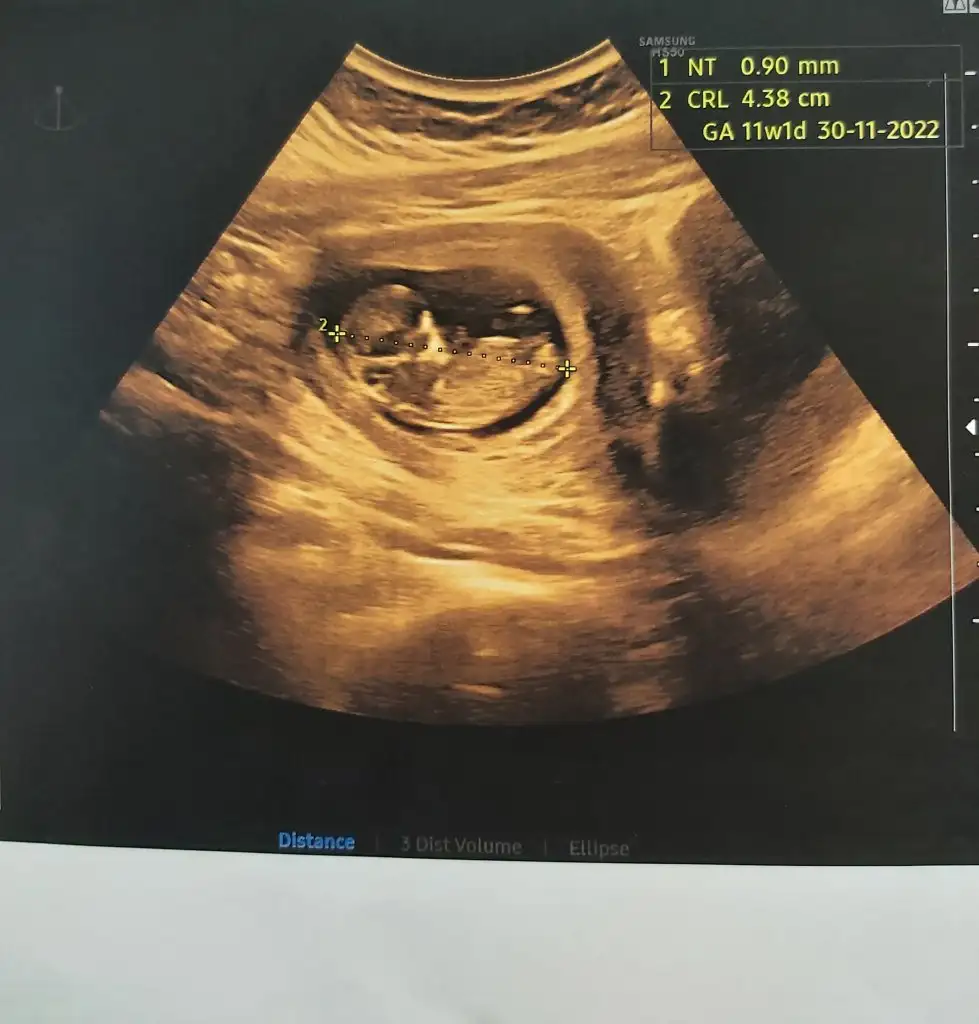

merahaba 11+3 karnımdan bakıldıSelam Kızlarbir çok kişi gruplardan beni bilir. Yine yetiştim imdatlara

5 ve 14. haftaya kadar olan ultrason fotolarınızı paylaşın. Vajinadan mı yoksa karından mı çekildiğini ve kaç haftalık olduğunu da mutlaka belirtin.

Merhaba :) bana 6.haftada erkek demiştiniz. Doktor da 12+3te erkek gibi dedi, tekrar bakabilir misiniz :)Hala kız gibi duruyorhadi bakalım inşallah kalbinden ne geçiyorsa o olur